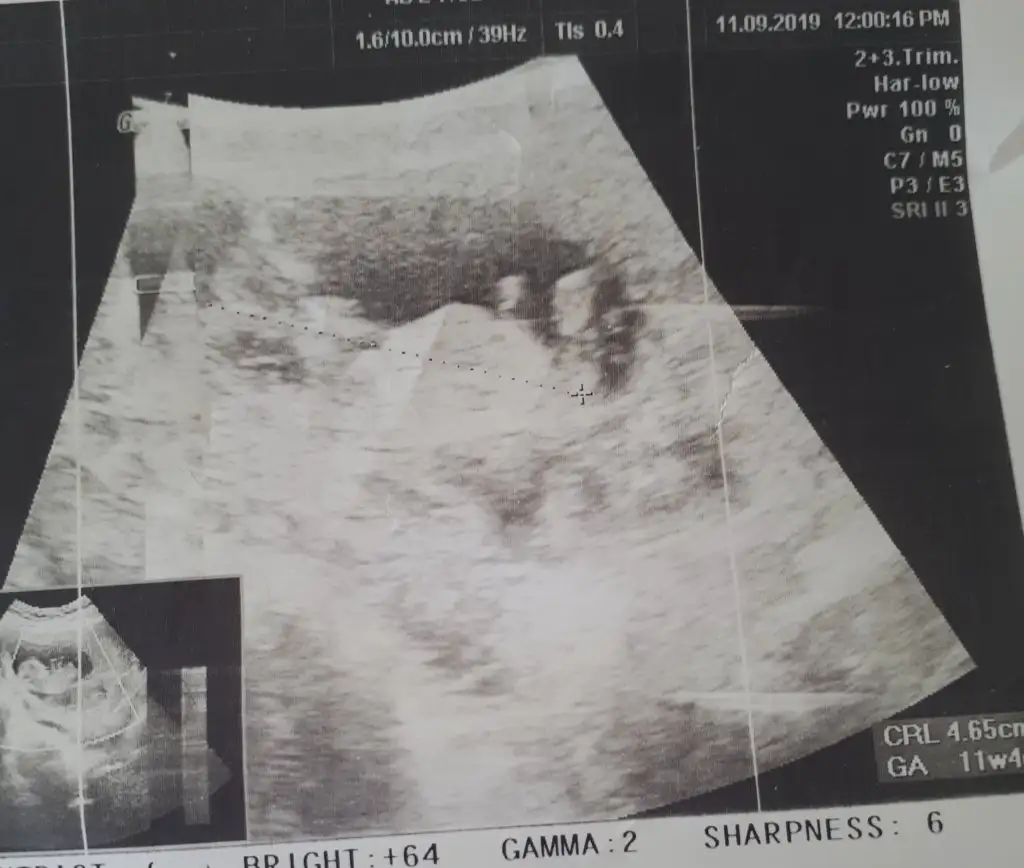

Kız gibibir fotograf karesi de bizden gelsin dr.henuz tahmin yapmadi siz neler goruyoyorsunuz

bir fotograf karesi de bizden gelsin dr.henuz tahmin yapmadi siz neler goruyoyorsunuz